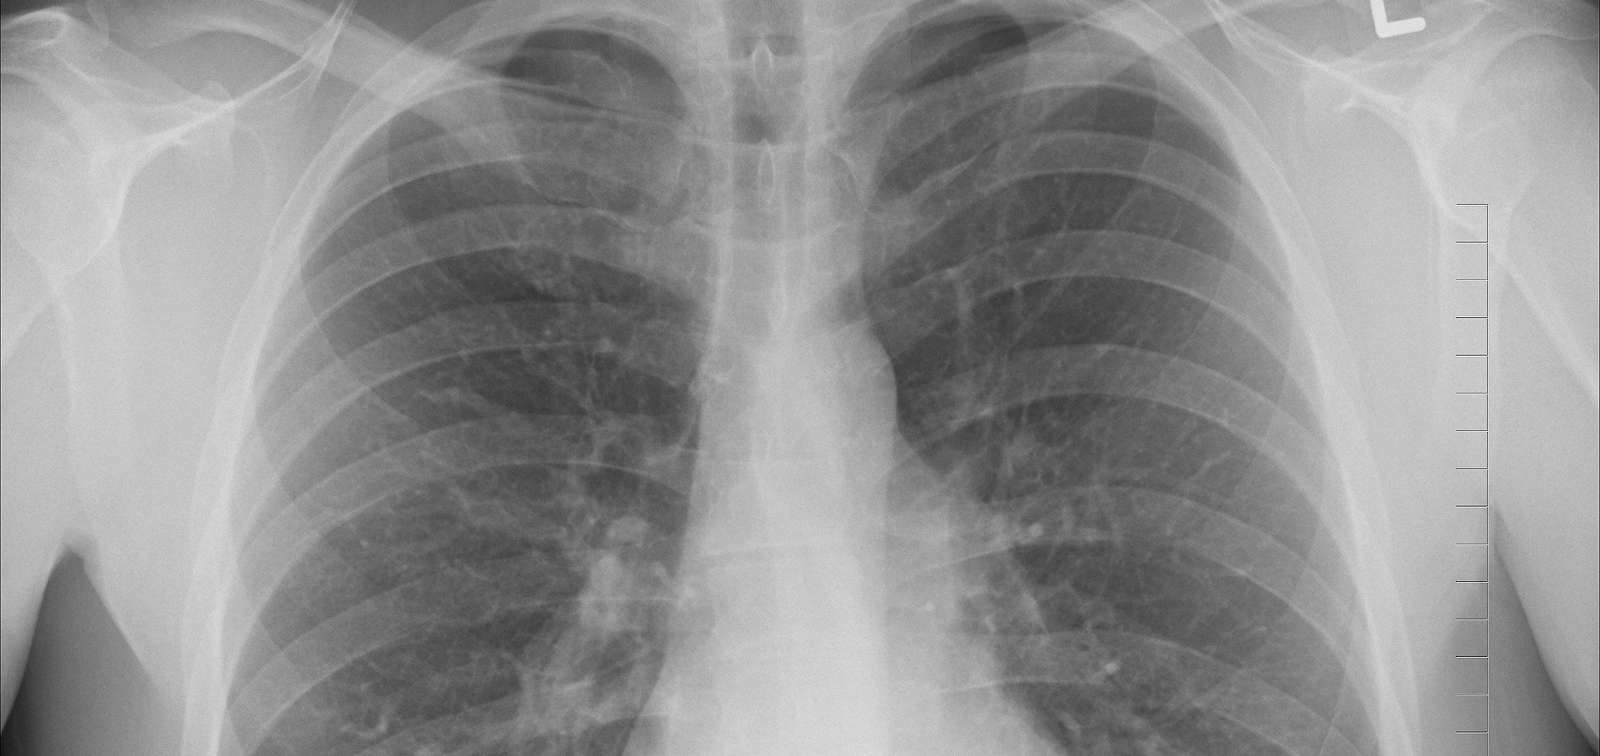

Radiografia pulmons

Foto: Oracast (Pixabay)

PreFIT aims to validate assays for improved prediction of progression from latent tuberculosis infection (LTBI) to active tuberculosis (TB) disease. Assays with high positive predictive value (PPV) for progression to TB disease have great potential for reducing TB morbidity and mortality in Africa by allowing scale-up of preventive treatment, which is becoming possible with shorter, safer preventive treatment regimens. PreFIT will achieve high PPV for progression to TB disease with a package of assays that diagnose incipient TB, a stage of LTBI progressing towards disease that can be halted with preventive treatment. These assays test for specific messenger RNA, C-reactive protein and hemoglobin on field-friendly platforms. PreFIT will take the next step in development of these novel and existing assays by validating them prospectively at point-of-care for their clinical performance, feasibility and cost in a cohort of TB-exposed household contacts. These contacts will be followed for 12 months for progression to TB disease, and we will compare test results among participants who do, versus participants who don’t progress to TB disease. In addition, PreFIT will validate iron homeostasis markers retrospectively on the samples collected in the cohort. Robust plans will ensure assay uptake and capacity building.